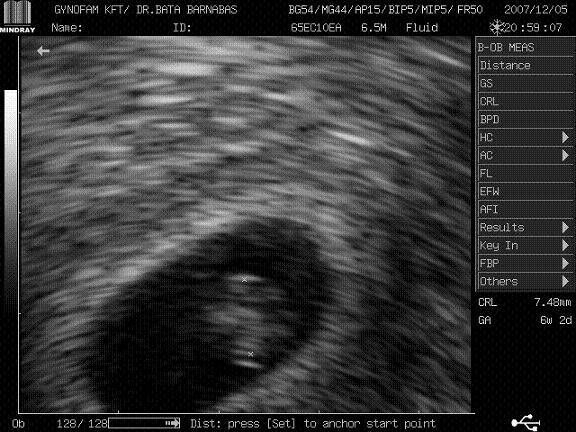

Gratulálok a kis Mütyürkétekhez. Akkor ezek szerint 1 babóci lesz????